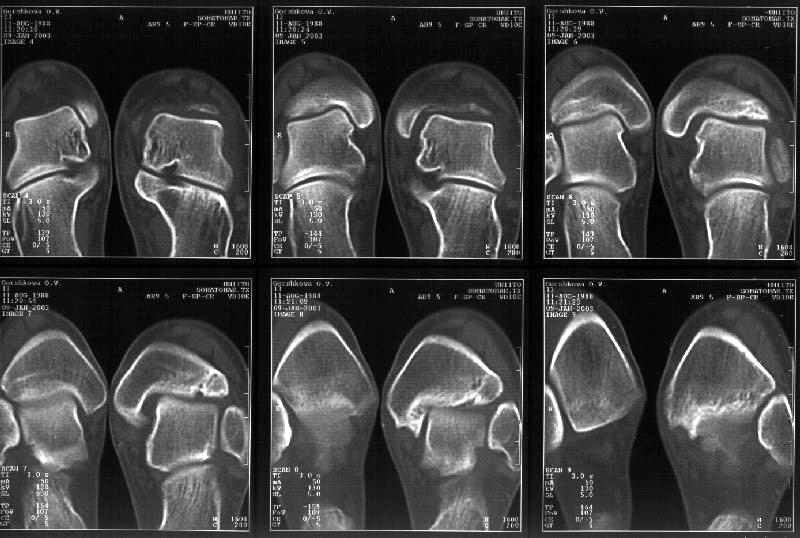

Отправитель: Alexander Chelnokov 19 Январь 2003, 22:34

Сегодня пациентке сделали сравнительную КТ. А ксиальные и Фронтальные срезы приложены. Ваше мнение?

Фронтальные

Аксиальные

На КТ я попытался изобразить скромными своими способностями (А)- место перелома, (С)- нормальный суставной зазор меж тараном и тремя его маллеолами. (В)- образовавшийся в результате перелома широкий раза в три зазор, позволяющий, по-моему, сублюксацию тарана при ходьбе. В свете данных КТ, критически важных, я бы предложил вертикальную остеотомию места перелома

задне-внутренним подходом и фиксацию мед. маллеола прижатым к тарану с помощью тонкого compression screw. После этого гипсовый сапожок и немедленное расхаживание ноги.